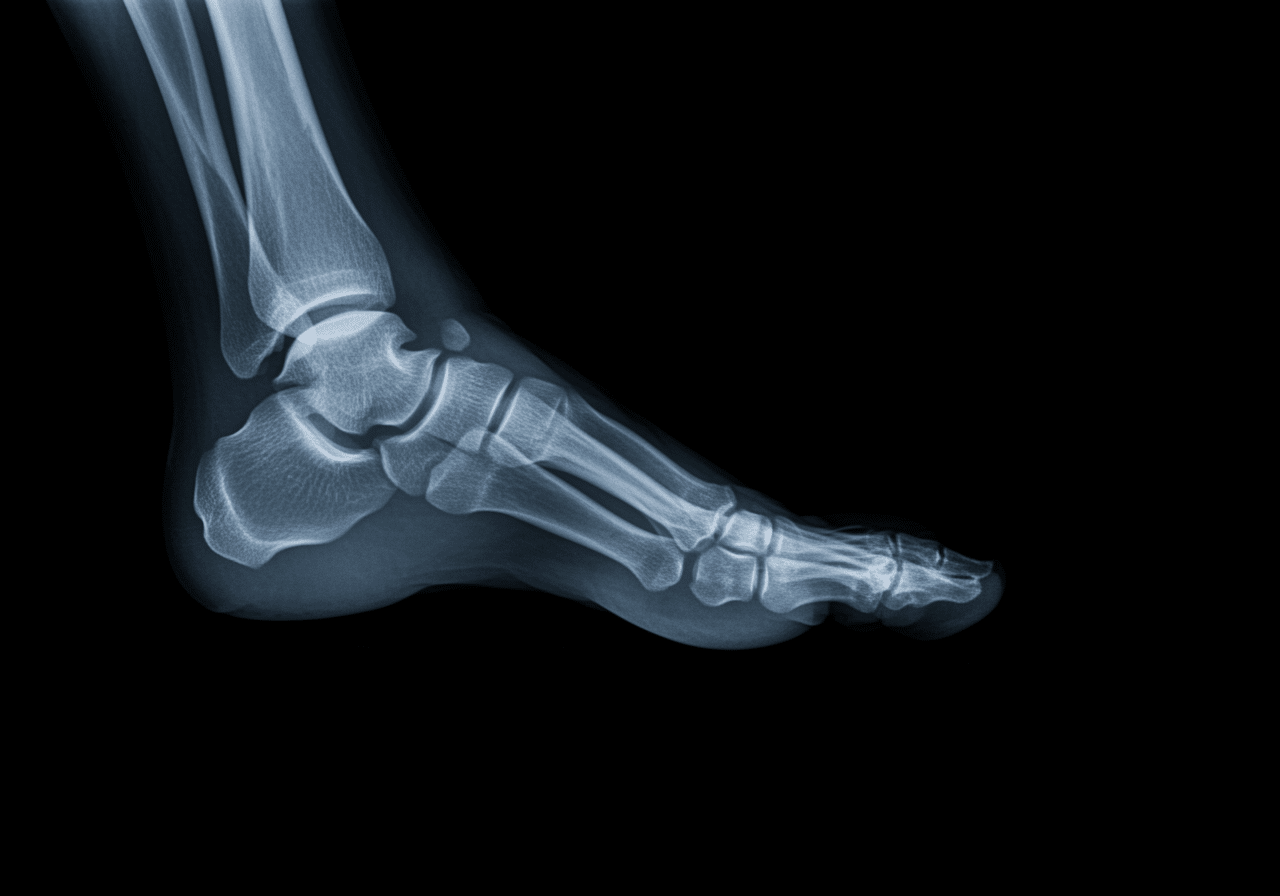

Advanced imaging through our comprehensive diagnostic capabilities provides CT scanning for pilon fractures assessing articular surface involvement, stress views identifying syndesmotic instability requiring surgical fixation, and foot x-rays including oblique projections identifying Lisfranc injuries that standard views cannot fully visualize. For calcaneal fractures, our emergency physicians utilize Bohler's angle and critical angle of Gissane measurements determining fracture severity and surgical necessity. This comprehensive approach explains why the American Academy of Orthopaedic Surgeons recommends emergency departments over urgent care for all ankle fractures requiring reduction, open fracture management, or neurovascular monitoring unavailable in limited-capability urgent care settings.